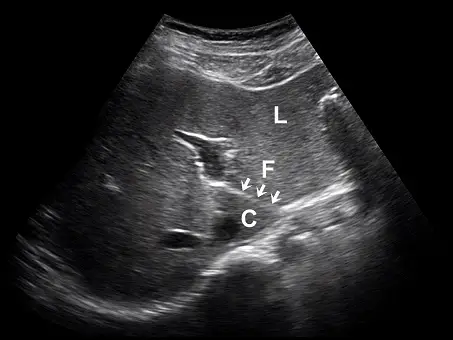

肝臟超音波橫向掃描時,在外側節段(lateral segment, L)與尾葉(caudate lobe, C)之間有一高回音裂隙(fissure, F),如下圖箭號處。此高回音裂隙與下列何者最有關係?

觀察題目提供的肝臟橫向掃描(transverse scan)超音波影像:

- 標記 L:位於影像較淺層(前方),為左肝葉的外側節段(lateral segment of left lobe,即 Couinaud 肝節段的 Segment II 或 III)。

- 標記 C:位於影像較深層(後方),為尾葉(caudate lobe,即 Segment I)。尾葉通常位於下腔靜脈(IVC)的前方。

- 標記 F 與白色箭頭:指示一條明顯的高回音(hyperechoic)線狀結構,剛好介於左肝外側節段(L)與尾葉(C)之間。此高回音特徵代表該處富含結締組織,在解剖學上正是分離這兩個構造的裂隙。

- (A) 靜脈韌帶(ligamentum venosum):正確。在胎兒時期,靜脈導管(ductus venosus)負責將缺氧血及部分充氧血引流至下腔靜脈以繞過肝臟。出生後,靜脈導管退化並形成靜脈韌帶。在超音波影像中,靜脈韌帶裂隙(fissure for ligamentum venosum)呈現一條高回音的亮線,其解剖位置正好位於左肝外側節段的後方與尾葉的前方,作為兩者的分界。與影像標記 F 完全吻合。

綜合上述的解剖位置與影像特徵,題目影像中位於左肝外側節段(L)與尾葉(C)之間的高回音裂隙(F),正是靜脈韌帶裂隙(fissure for ligamentum venosum)。因此,該構造最主要與靜脈韌帶(ligamentum venosum)有關。